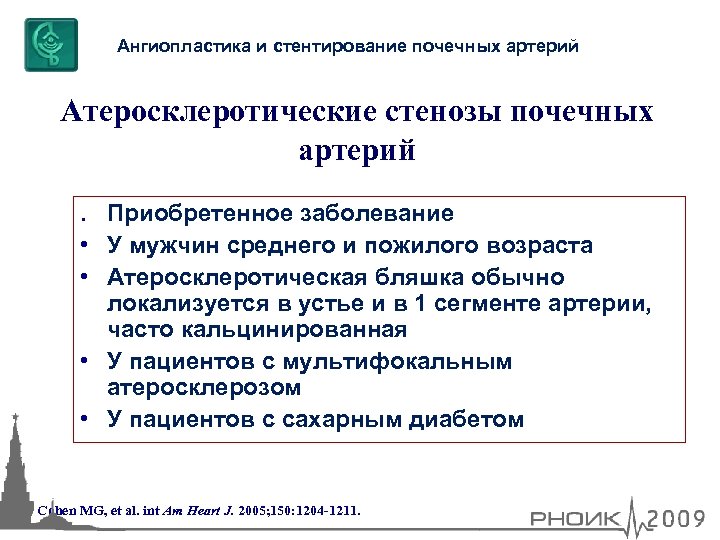

Ангиопластика и стентирование почечных артерий Атеросклеротические стенозы почечных артерий. Приобретенное заболевание • У мужчин среднего и пожилого возраста • Атеросклеротическая бляшка обычно локализуется в устье и в 1 сегменте артерии, часто кальцинированная • У пациентов с мультифокальным атеросклерозом • У пациентов с сахарным диабетом Cohen MG, et al. int Am Heart J. 2005; 150: 1204 -1211.

Ангиопластика и стентирование почечных артерий Атеросклеротические стенозы почечных артерий. Приобретенное заболевание • У мужчин среднего и пожилого возраста • Атеросклеротическая бляшка обычно локализуется в устье и в 1 сегменте артерии, часто кальцинированная • У пациентов с мультифокальным атеросклерозом • У пациентов с сахарным диабетом Cohen MG, et al. int Am Heart J. 2005; 150: 1204 -1211.